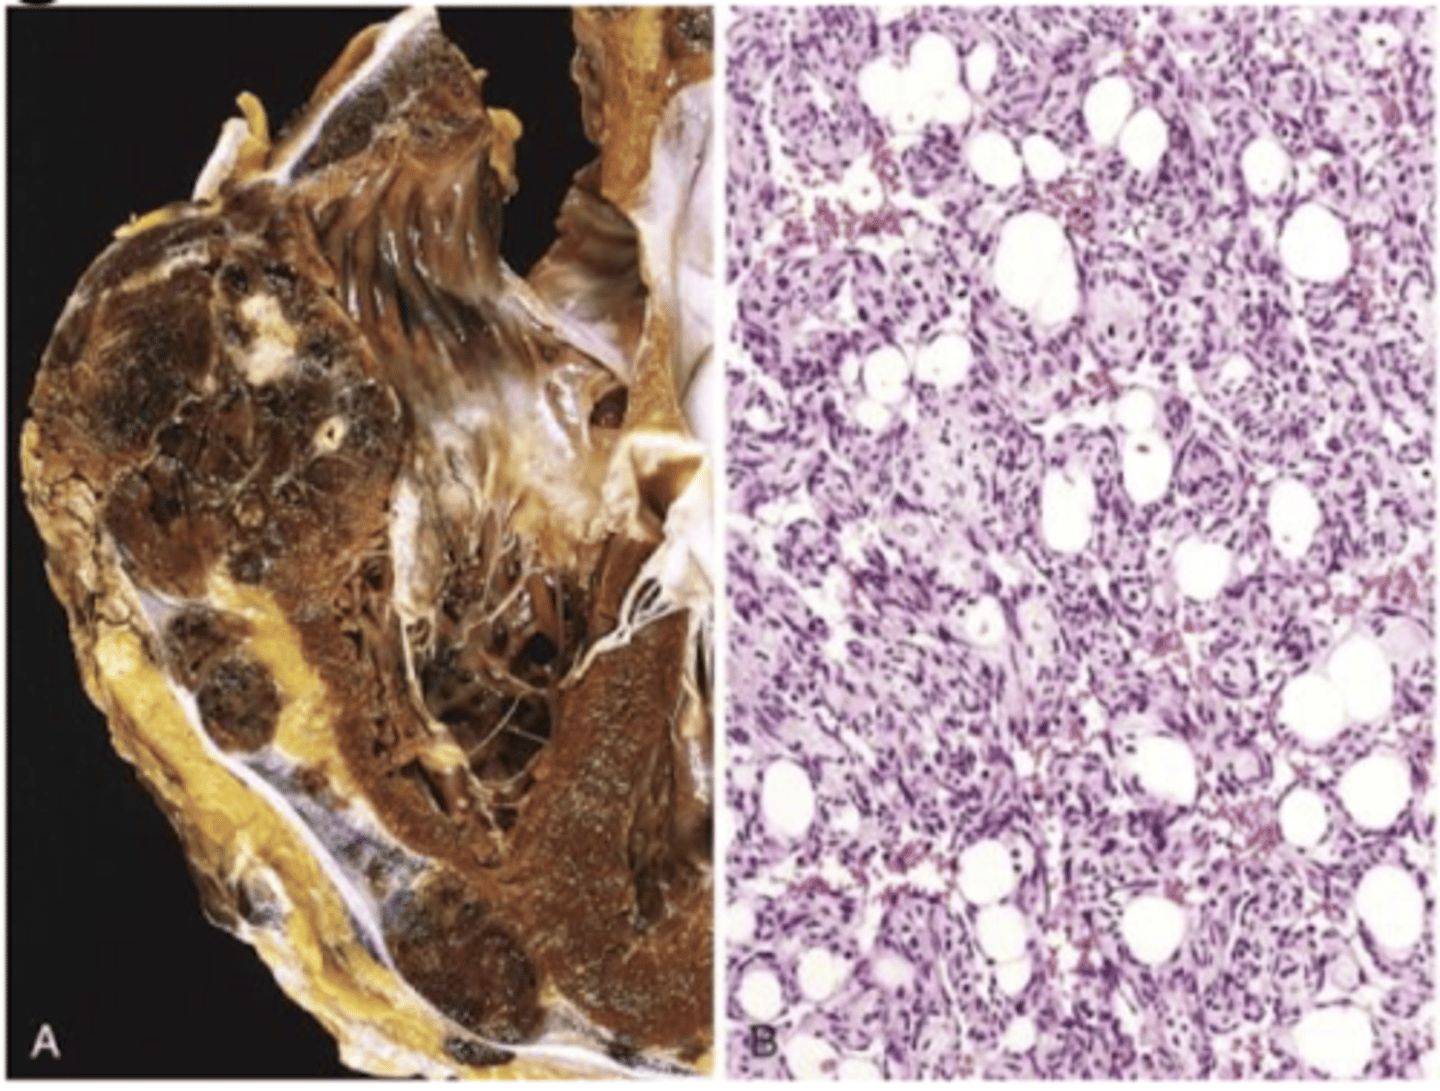

angiosarcoma

malignant endothelial neoplasm

appearance of angiosarcoma

starts as small papule

progresses to large, fleshy red tan to gray white lesions with blurred margins, necrosis, hemorrhage

angiosarcoma can arise from

lymphedema

hepatic angiosarcoma (carcinogenic exposure)

CD31 (vWF)

endothelial origin

angiosarcoma